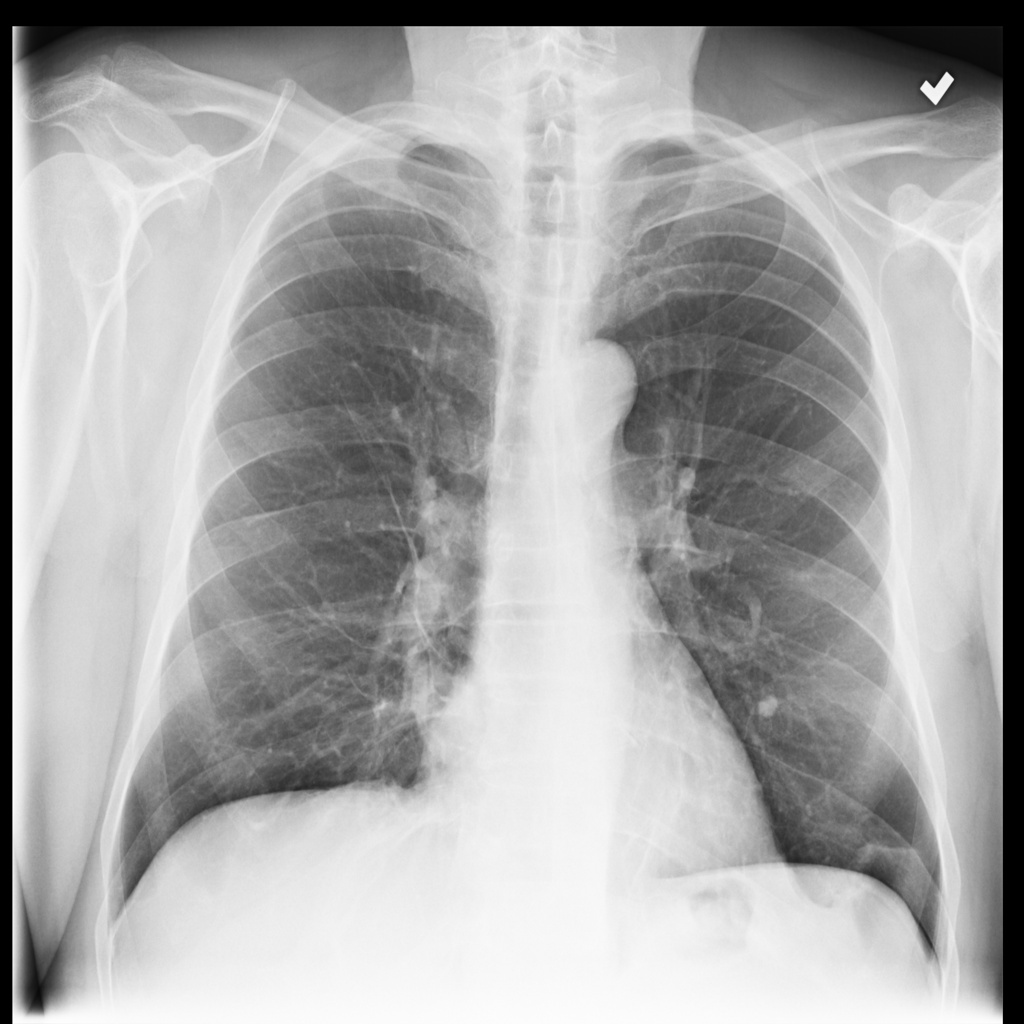

Table 4: Model prediction and reasoning.

Comparison between final prediction and the model reasoning.

Question: What disease is/are shown on the right of lung?

Short answer: Pneumonia Grounth truth: The image shows pneumonia in the right lung, characterized by areas of increased opacity due to fluid accumulation or inflammation. This condition can result from various infectious agents, leading to symptoms such as cough, fever, and difficulty breathing. The presence of such opacities indicates that the lung tissue is affected, which is typical in pneumonia cases. [Uncaptioned image]

Model reasoning: The image is a chest X-ray, and the right lung appears to have a darker, more opaque area compared to the left lung. This is indicative of a lung opacity, which can be caused by various conditions such as pneumonia, lung cancer, or other lung diseases. It is important to consult with a healthcare professional for a proper diagnosis and treatment plan.

Model final prediction: pneumonia, lung cancer and other lung diseases.